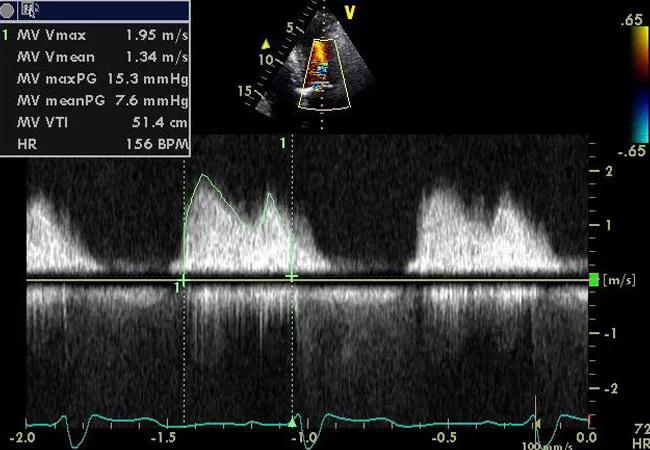

Long-term survival following surgery for mitral valve disease is substantially reduced among patients with radiation-associated cardiac disease (RACD) compared with the general population of patients undergoing mitral valve surgery, according to a new analysis from Cleveland Clinic.

To help fill that data gap, he and colleagues identified and studied patients with RACD who underwent mitral valve surgery at Cleveland Clinic from 2000 to 2017. During that period, 146 patients with RACD developed significant mitral valve disease requiring surgery. All of these patients were free of cancer recurrence at the time of surgery and had complete clinical and echocardiographic data.

“This analysis helps confirm that the increased morbidity and mortality observed with radiation-associated cardiac disease extends to outcomes of patients requiring surgery specifically for mitral valve disease,” concludes Dr. Desai. “Earlier identification of RACD by way of routine clinical and echocardiographic surveillance may be helpful in blunting its impact in this population, as may emerging percutaneous valve replacement procedures.”